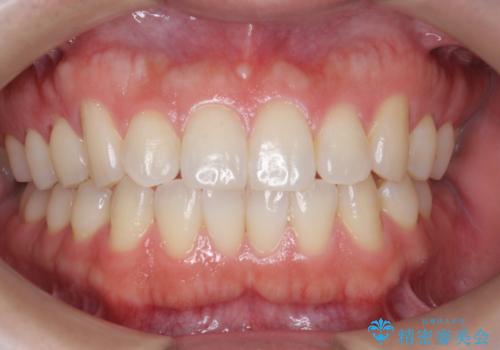

オフィスホワイトニングで、歯を白く!

- ホワイトニングで、ご自身の歯を白くしたいと来院されました。

医院で行う、オフィスホワイトニングで歯が白くなり、喜んでいただけました。